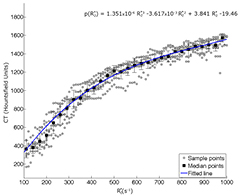

we sorted the pairs in bins of size 10 s−1 and calculated the median for each patient in each bin. We then fitted a third order polynomial to the median points in order to obtain a mapping from  to CT HU values. The median points (±standard deviation to the mean) are shown together with the fitted polynomial in figure 2. Using this mapping, for each new patient we converted the values in the

to CT HU values. The median points (±standard deviation to the mean) are shown together with the fitted polynomial in figure 2. Using this mapping, for each new patient we converted the values in the  map greater than 100 s−1 to CT HU, and from there, scaled the image to LAC (Carney et al 2006). To limit bias we excluded bone from voxels with high likelihood of being soft tissue voxels by thresholding nUTETE2 at 1200, assuming the bone signal had fully decayed in this image.

Figure 2.  versus HU scatter plot with sampled points shown for each patient in gray (n = 10). Every third median bin-value showed with black squares. Standard deviation to the mean value is shown with black error bars. A 3rd order polynomial fit to the median points is shown with the blue line, r2 = 0.93.

versus HU scatter plot with sampled points shown for each patient in gray (n = 10). Every third median bin-value showed with black squares. Standard deviation to the mean value is shown with black error bars. A 3rd order polynomial fit to the median points is shown with the blue line, r2 = 0.93.